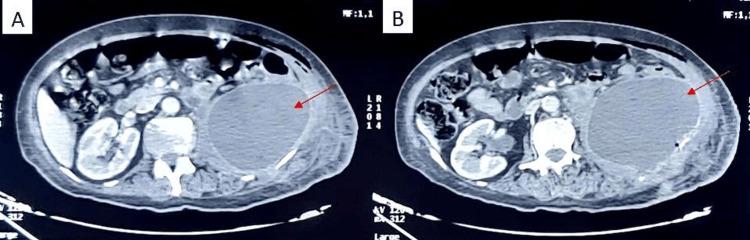

This report discusses a rare case of retroperitoneal infection caused by in a 68-year-old immunocompetent woman following a nephrectomy.  was identified through meticulous mycological examination. This case challenges the typical association of infections with immunocompromised patients, emphasizing its potential pathogenicity in immunocompetent individuals. The importance of accurate identification, especially in postoperative infections and broad-spectrum antibiotic contexts, is highlighted, emphasizing the need for a thorough diagnostic approach in such cases.

A Rare Case of a Retroperitoneal Abscess Due to Trichosporon spp. in an Immunocompetent Patient.